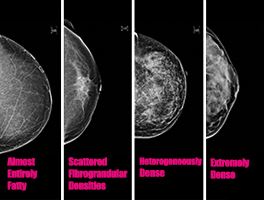

Dense breast tissue refers to how your breast tissue looks on your mammogram (as opposed to fatty, or nondense, breast tissue). The density of your breast tissue depends on how much glandular tissue, fibrous tissue and fat is in your breasts. If you have more fibrous or glandular tissue than fat, your breasts are considered dense. Breast density isn’t anything you can control or treat. It just is what it is.

The big deal is that dense breast tissue may increase your risk for breast cancer. Researchers aren’t sure why, but rest assured they’re trying to figure out the connection. On a mammogram, opens new tab, dense breast tissue appears as solid white areas. So do cancer masses. See the problem? Sometimes it’s tough for a radiologist to tell the difference, and you may need further imaging tests.